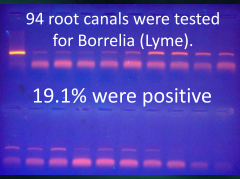

They also provide a hiding place

for Lyme’s Borrelia to embrace

Lyme does its damage, then hides away

in root canals, they love to play

They stay in there for months on end

for there is no immune system to defend

Then drop your resistance for a minute

and you can no longer defend it